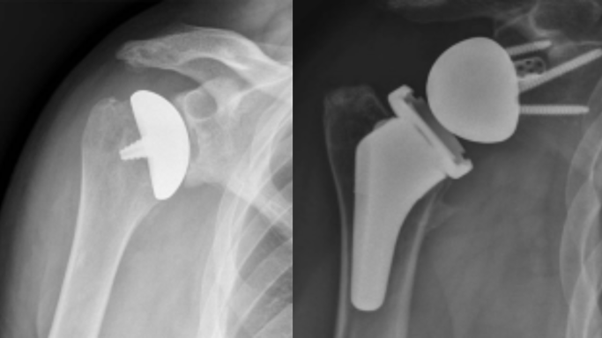

Reverse Total Shoulder Replacement (RTSA) is a specialised surgical procedure designed to treat shoulder arthritis, rotator cuff tears, and severe joint damage that cannot be effectively addressed with conventional shoulder replacement methods. This innovative surgery reverses the natural mechanics of the shoulder joint, allowing the deltoid muscle to take over the function of the damaged rotator cuff, improving shoulder function and alleviating pain.

Reverse Total Shoulder Replacement involves switching the normal ball-and-socket mechanics of the shoulder joint. The ball (humeral head) is removed and replaced with a socket, while the socket (glenoid) in the shoulder blade is replaced with a ball-shaped prosthesis. This reversal allows the deltoid muscle to perform movements that are usually controlled by the rotator cuff, particularly in cases of irreparable rotator cuff tears.